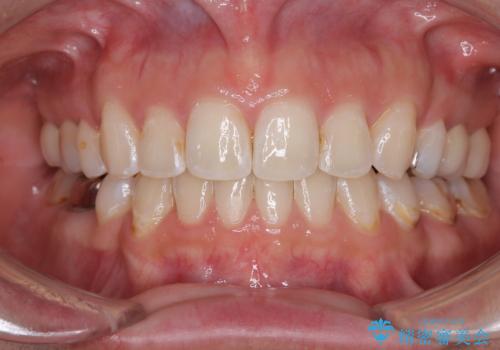

- 口が閉じられない 抜歯矯正で前歯の突出感を改善

- 出っ歯と奥歯のむし歯 ワイヤー装置での抜歯矯正とセラミック治療

- 横顔の印象を変えたい ワイヤー装置での抜歯矯正